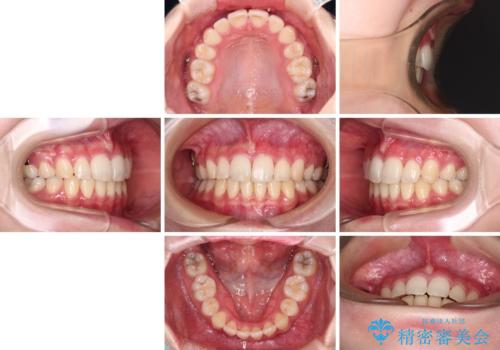

治療途中で転院 抜歯矯正の仕上げ治療

- 7ヶ月

- 5-10回

出っ歯を抜歯矯正にて治療をしていらっしゃいましたが、抜歯スペースが少し残っていたため、閉じて歯列を仕上げていくこととしました。